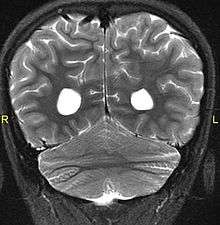

Aside from the physical characteristics of the eyes there is also less sensation in the eyes when stimulated.[4] The eyes also show low motor control(ataxia).[4] Along with ataxia comes a lack of coordination or ability to judge the distance of objects(dysmetria).[6] MRIs have shown a fusion of the cerebellar hemispheres(rhombencephalosynapsis) and absence of the cerebellar vermis in every case of Gomez-Lopez-Hernandez syndrome.[4][7][8] The cerebrum is not fused. Also absent are the trigeminal nerve of the trigeminal cave and the foramen rotundum, causing abnormal sensations on the forehead and the corneas.[6][8] One Gomez-Lopez-Hernandez Syndrome case in Japan also presents fever-induced seizures.[9] Others may or may not present with non-fever-induced seizures.[4] Malformations of motor centers in the brain cause reduced muscle strength(Hypotonia).[8] Eleven of fifteen people in one study showed moderate-to-severe intellectual disability.[6] In cases where it has been noted, head nodding is present.[6] Hydrocephalus and enlargement of the ventricular system is consistently present.[6] A reduced corpus callosum is present in some cases(agenesis of the corpus callosum).[6]